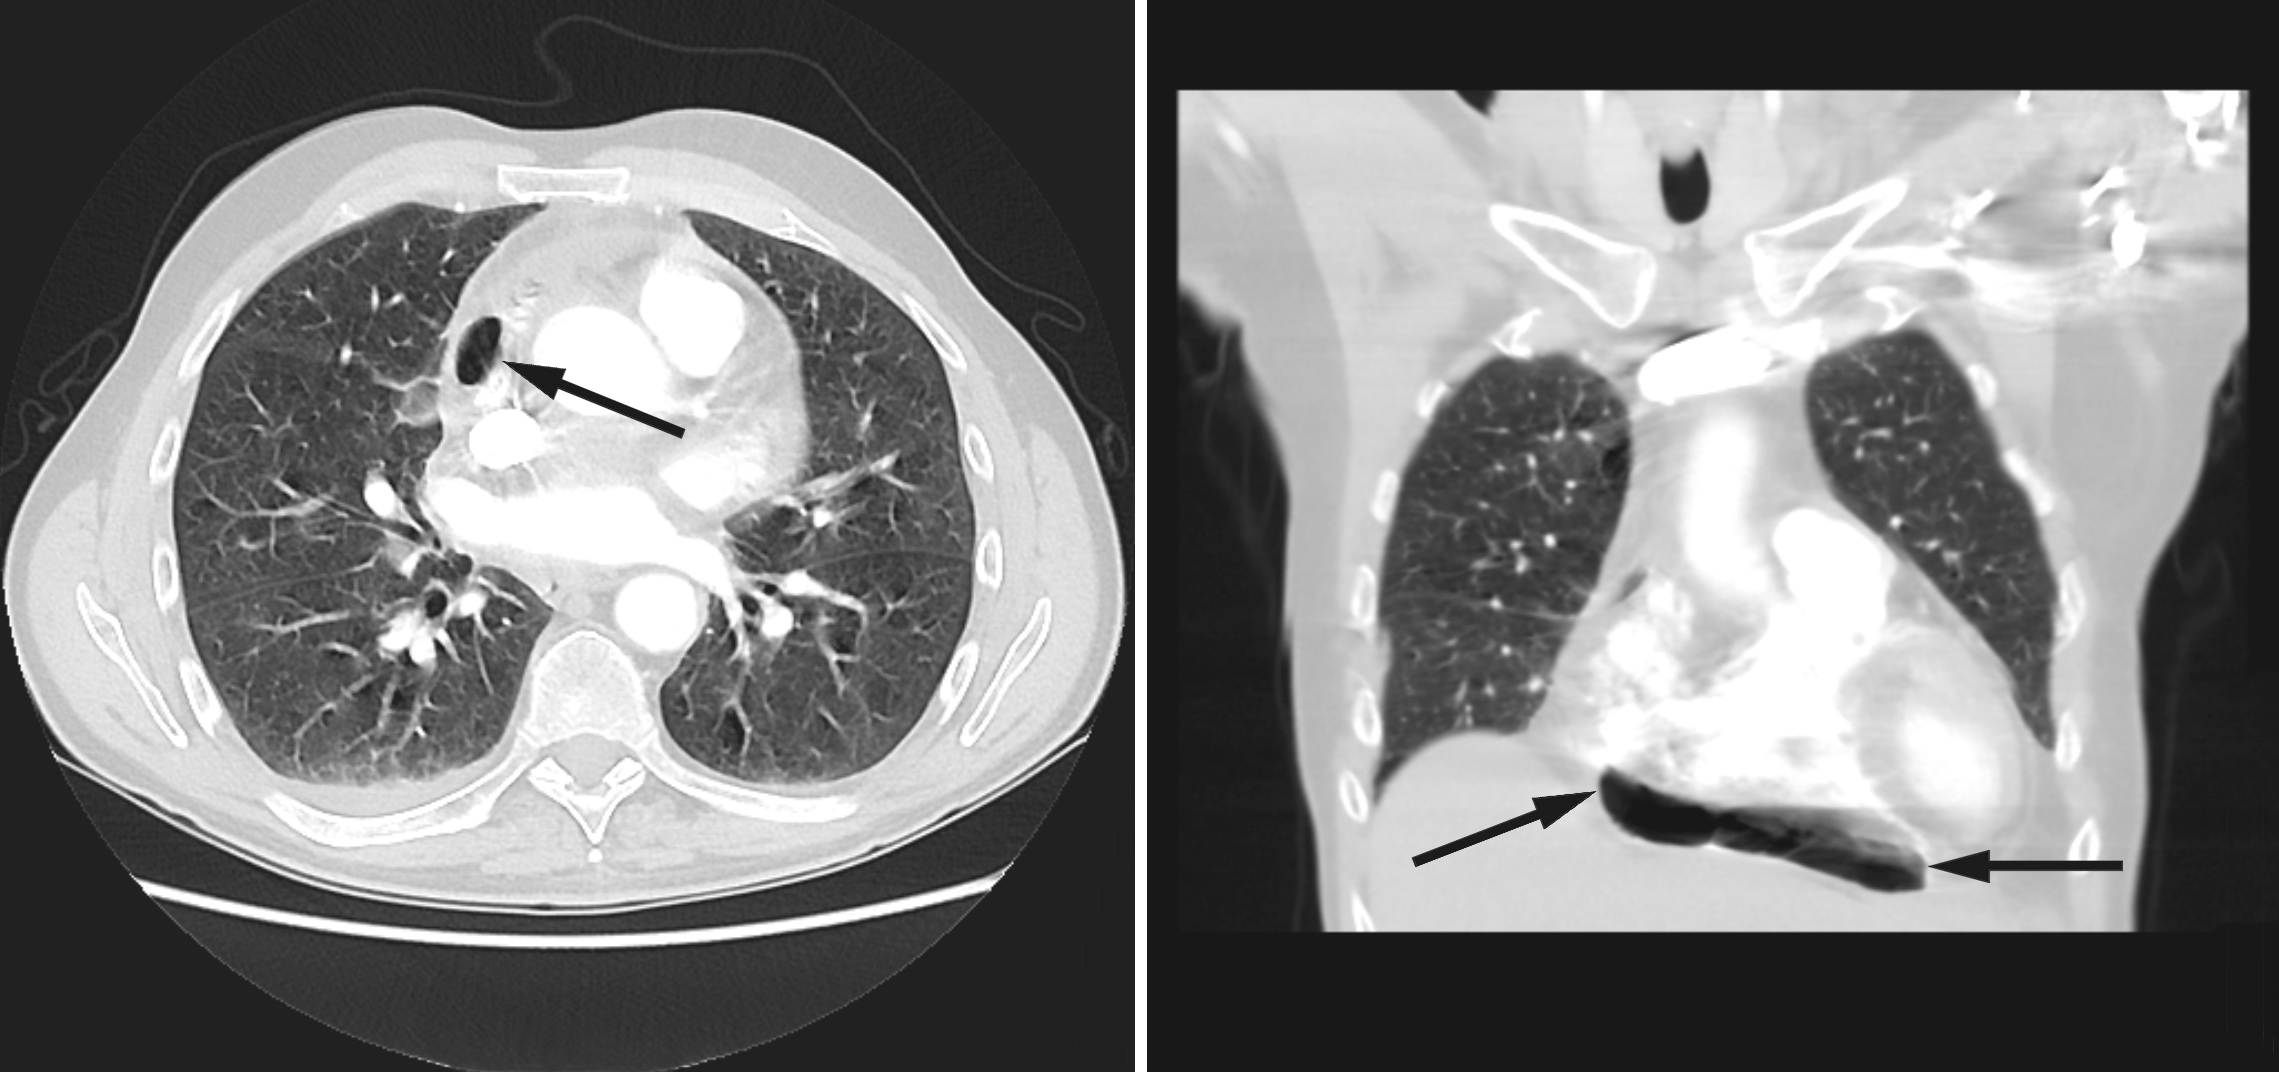

På mistanke om infeksjonsutvikling med utgangspunkt i lever/galleveier eller pancreas, ble intravenøs behandling med cefotaxim 1 g x 4 startet. Ultralyd abdomen viste slanke galleveier, men radiolog anbefalte CT abdomen for endelig avklaring. Dette ble utført samme dag supplert med CT thorax med lungeemboliserie. Underveis i denne undersøkelsen fikk pasienten akutt økende dyspné med metningsfall til 70 %, takypné med respirasjonsfrekvens på 22/minutt og takykardi med puls på 130 slag/minutt, ledsaget av kraftig forverring av smertene i høyre hemithorax. Onkolog og anestesilege ble tilkalt. Med ventilasjonsstøtte på maske klarte pasienten å gjennomføre undersøkelsen som viste fri luft i mediastinum, hovedsakelig i perikard, samt noe perikardeffusjon (fig 1). Lekkasjestedet kunne ikke påvises. I buken var det ingen fri luft.

I foreliggende pasienthistorie var det spredning av både kreftceller og bakterier til epi- og perikard. Ved obduksjonen ble det ikke påvist økt luft/gass i perikard. Dette kan likevel ikke utelukkes, da man ikke spesifikt undersøkte for dette. Fistel mellom perikard/mediastinum og øvre gastrointestinalkanal eller trachea ble heller ikke avdekket, skjønt en liten åpning kan heller ikke utelukkes. På CT-undersøkelsen tatt dagen før dødsfallet er luft godt synlig (fig 1), men det var ikke mulig å identifisere lekkasjestedet. Sannsynligvis har maligne celler erodert perikard og epikard fra mediastinum, som ledd i det infiltrative vekstmønsteret, hvilket kan ha skapt en ventil for bakterier og luft. Fri luft/gass kunne også tenkes å ha oppstått som et (bi-)produkt av en bakteriell superinfeksjon med autolyse og vekselvirkning mellom bakterielt toksin og karsinomceller. Infeksjoner med gassproduserende bakterier i tarm eller bløtvev gir imidlertid som regel kun små gasslokulamenter på CT. Mikrobene som ble påvist er heller ikke typisk gassproduserende. Pasienten hadde ikke gjennomgått invasive prosedyrer utover biopsitakning fra lymfeknuter i øvre mediastinum, som ble utført tre uker tidligere. Denne prosedyren er rapportert å kunne forårsake penumomediastinum, men da som en akutt komplikasjon (5). Bruk av steroider og antibiotika i kombinasjon kunne potensielt forårsaket kolonisering eller infeksjon av sopp i oesophagus, med påfølgende ruptur. Det ble derimot ikke sett tegn til dette under obduksjonen. Pneumomediastinum kan utløses av kraftige hosteanfall, uten at en slik rift i luftveiene er synlig på CT. Iomeron, kontrastmidlet som gis i forbindelse med CT, kan utløse hoste, men dette er ikke journalført som et fremtredende symptom hos denne pasienten.